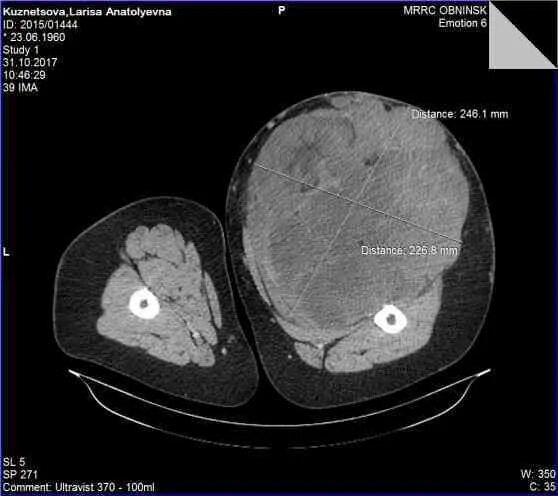

Кт тканей